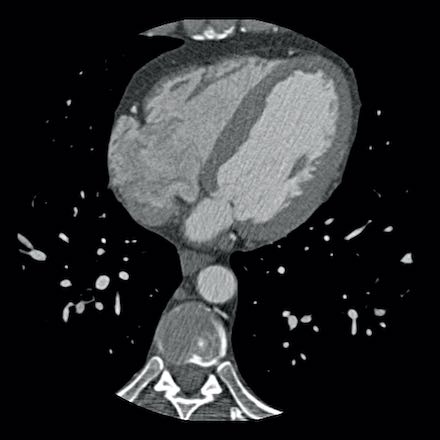

Continue with the next images…

A: ICA correlates with CTA and shows an 80% stenosis in the mid LAD

(white arrows) and a 60% stenosis in the D2 branch (black arrows). The D2

stenosis was overestimated on CTA.

B: PCI was performed during which a drug eluting stent (DES) was

implanted with good results (white arrows).